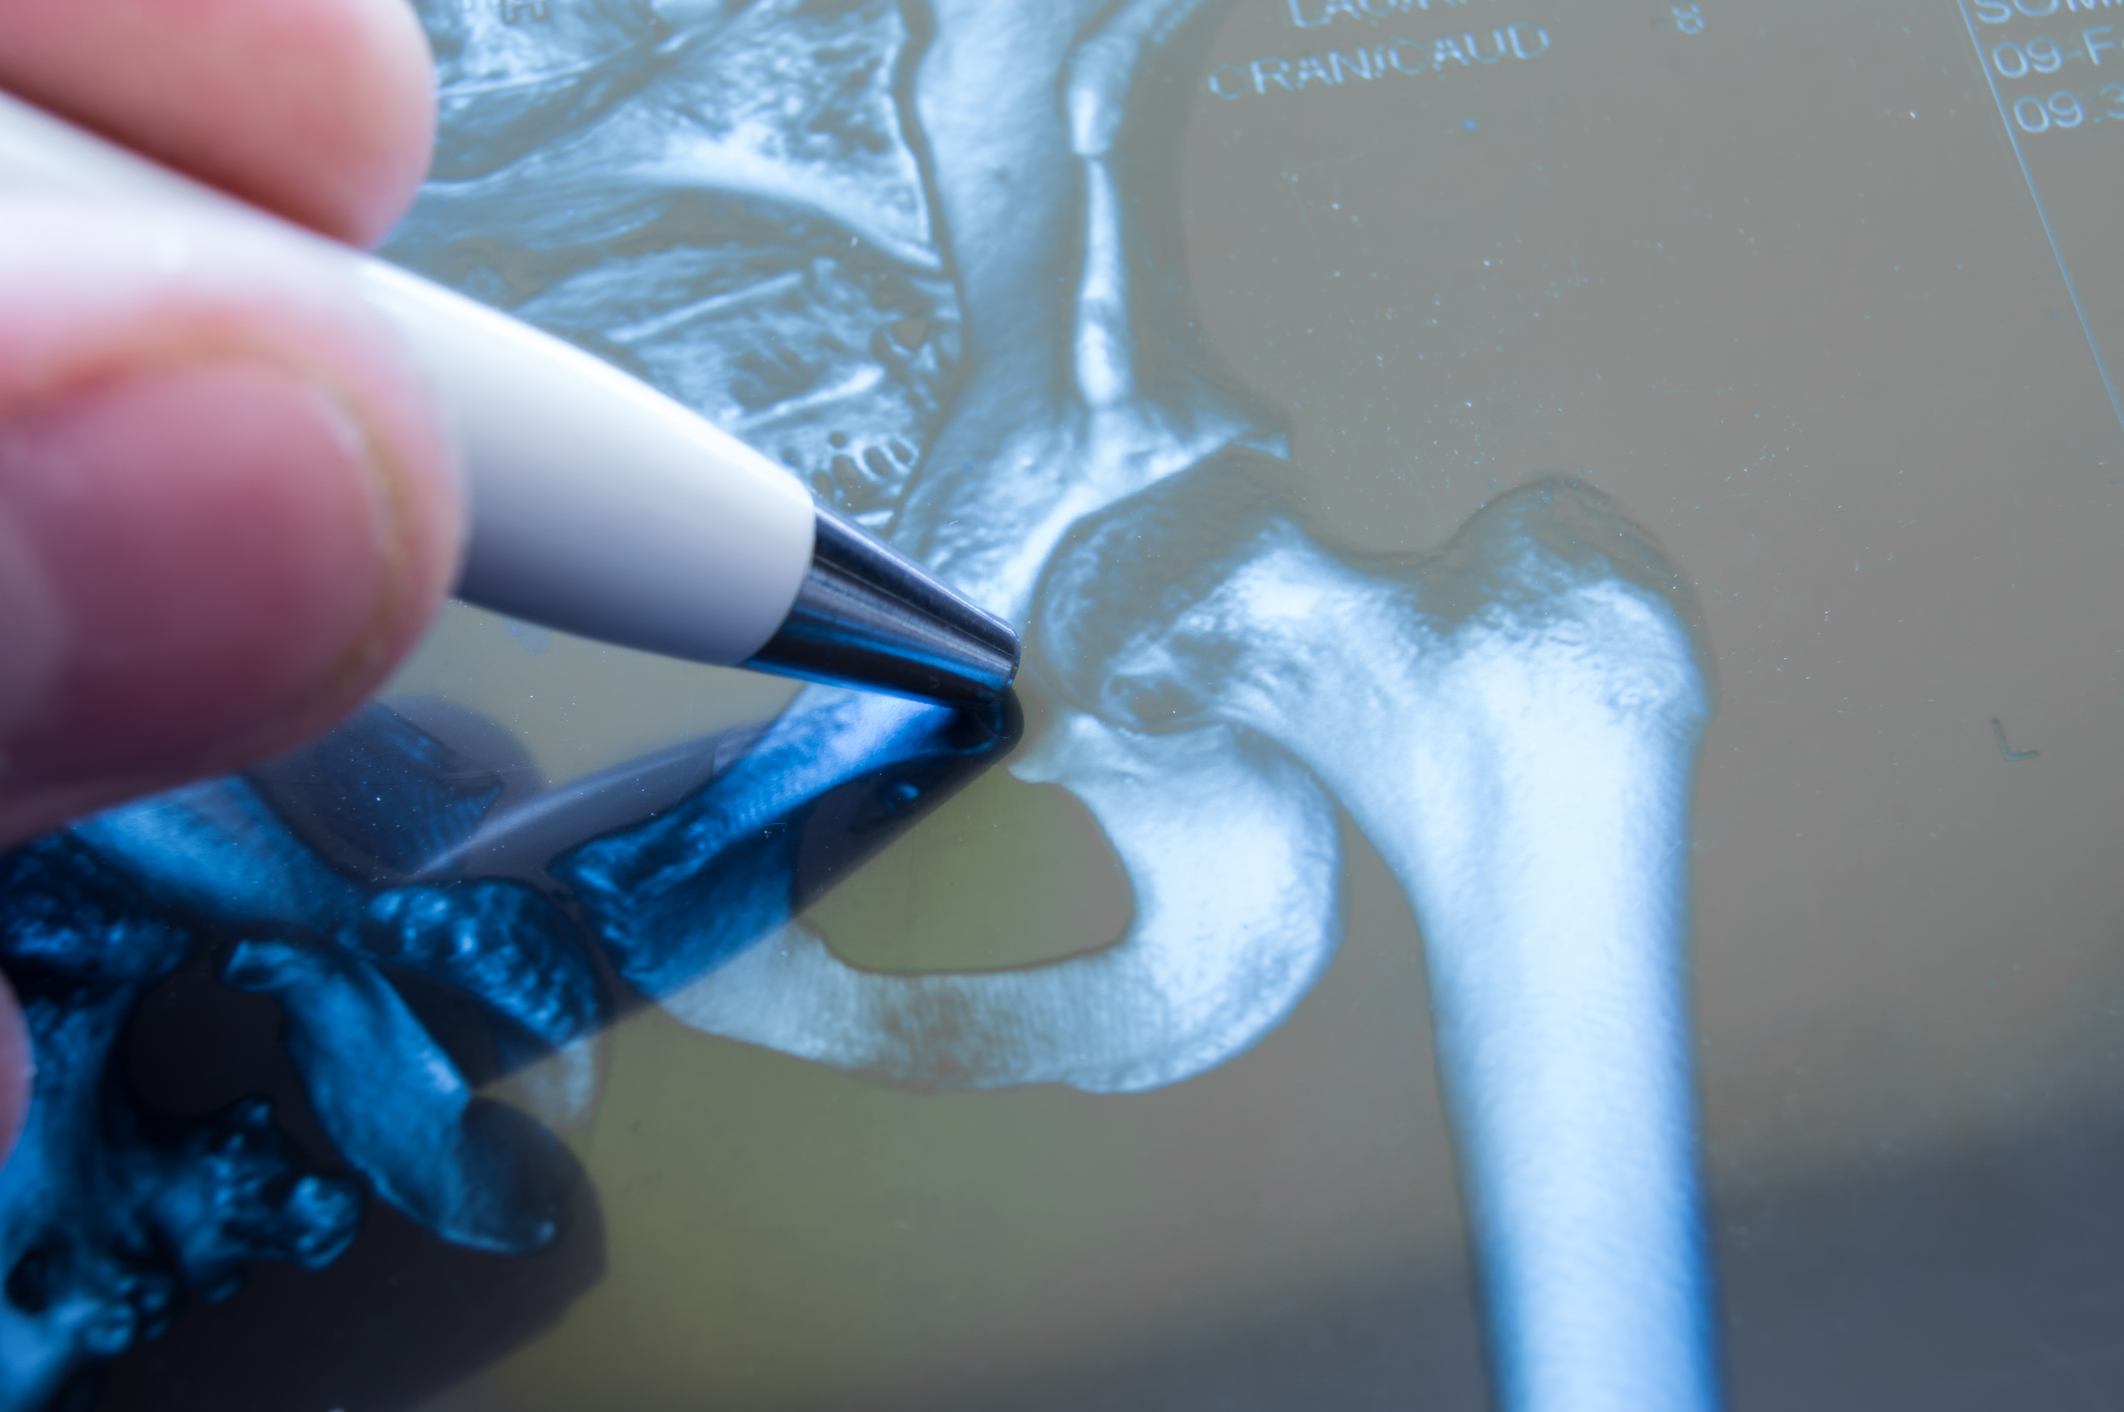

As we get older, our bodies weaken, bones become sore, and joints break down. Hip and knee problems are common conditions of aging. In fact, in the past decade millions of Americans have had hip replacement surgeries. Unfortunately, some defective artificial hips have caused patients more suffering than their original hip ailments. For one recent example, many patients who received the Birmingham Hip Resurfacing System by Smith & Nephew have had to undergo revision surgeries to cure new and unanticipated problems relating to the medical device. Many of these people have filed lawsuits.

Smith & Nephew’s Birmingham Hip Resurfacing System

Smith & Nephew designs and markets medical devices. One of the medical devices Smith & Nephew manufactures is a joint replacement system. An example of a joint replacement system is a hip implant. The Birmingham Hip Resurfacing (BHR) System is an artificial hip replacement made of metal components. BHRs have been used since 1997. The FDA approved BHRs for use in the United States in 2006; this approval was conditioned on Smith & Nephew reporting and analyzing adverse events, negative side effects, and complaints regarding the BHR. Just like any other medical device or medicine, the BHR must not provide false information (or false hope) to patients about what the device can accomplish.

These recalls are due to medical complications and problems caused by the unexpected wear of the metal device over time. More specifically, as the metal artificial hip bends and moves, there is friction between the metal pieces which causes metal debris to collect in the joint and move to the bloodstream. Metal debris in the body causes pain, swelling, immune reactions, and other serious medical complications. Also, as the artificial hip moves and deteriorates, the implant may begin to loosen and require yet another hip surgery (“revision surgery”).